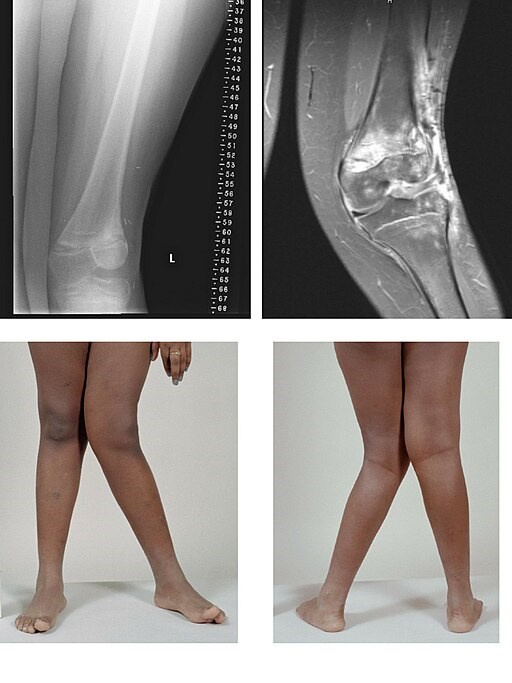

The medical term for knock knees is 'genu valgum' - genu meaning 'knee' in Latin, and valgum meaning 'bending outwards'. In knock knees, if the knees touch it is the lower leg which seems bent outwards. So if you have knock knees you are unable to stand with your knees AND your ankles together.

As the child's leg bones grow and develop, they then tend to take on a 'knock-kneed' shape. Now if their knees are together, their feet and ankles are apart. It tends to be most obvious around the age of 3 or 4 years, usually gradually improving to the correct position after that, as the child stands for longer periods of time. Knock knees are normal up to the age of 7 or 8 years, although the condition may last longer.

© BioMed Central, CC BY 2.0, via Wikimedia Commons

By BioMed Central, CC BY 2.0, via Wikimedia Commons